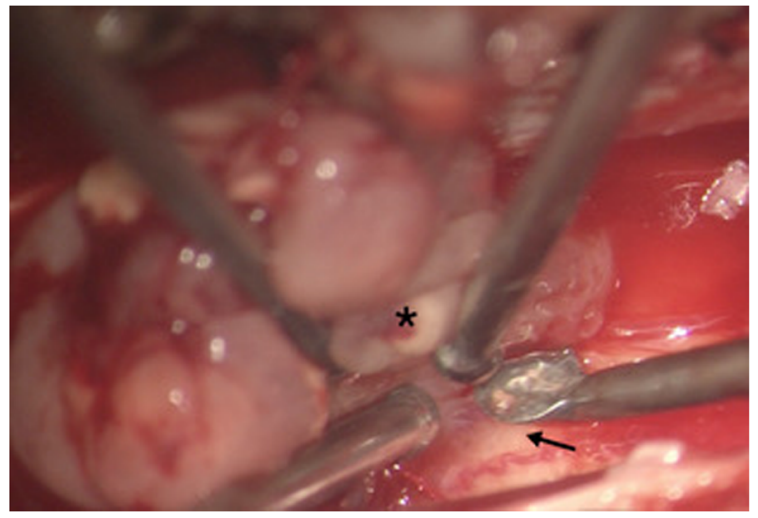

为进行组织诊断,进行了T7-T8椎板切除术以部分切除肿瘤。一旦病变被确定为毛细胞性星形细胞瘤,就继续对肿瘤进行切除。残余肿瘤分两个阶段切除。在一开始手术中,从T4-T10行多层椎板切除术。在硬脑膜中线开孔后,发现肿瘤呈浅银色附着在脊髓上(图2)。我们进行了细致的显微手术切除,将肿瘤从脊髓中分离出来。肿瘤和脊髓之间有一个可识别的平面,这便于顺利切除肿瘤,除了某些区域肿瘤似乎更粘连,并可能侵犯脊髓的pial覆盖。在这些位置,肿瘤被从脊髓上切除,只留下一层薄的肿瘤。随后,我们做了C4-T3椎板切除术来进行二次切除和切除剩余的肿瘤。

图2。术中图像。术中图像(放大5倍)显示肿瘤(*),平面可识别,与正常脊髓容易分离(↑)